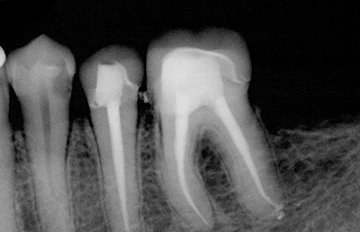

Root Canal Therapy

Root canal treatment is a restorative procedure that is performed to prevent the extraction of a tooth and tooth infections. It should commonly be followed by crowns, dental fillings, or inlays.